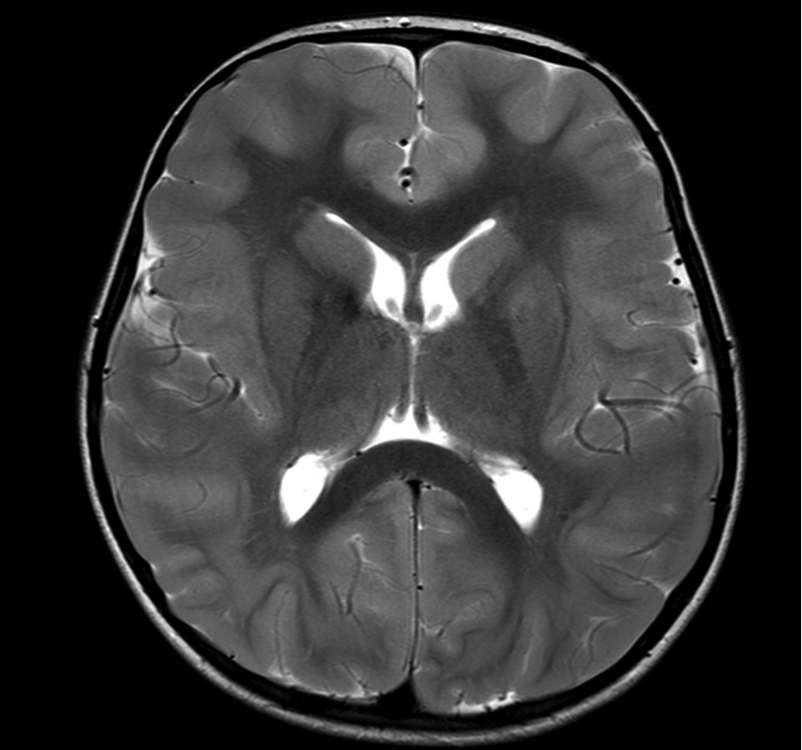

Whilst subcortical band heterotopia may be seen on USS and CT (depending on severity), MRI is the imaging of choice for assessing the detail and associated structural abnormalities. MRI should include thin slice volumetric T1-weighted images, axial and coronal T2-weighted and FLAIR images.

Imaging characteristics of subcortical band heterotopia:

• a band of grey matter is seen, located between the ventricle and cortex, this can be of variable thickness (can be subtle in some areas), and may be duplicated (i.e. a double band) in the temporal lobes

• the overlying cortex may be normal or may show shallow sulcation.

• Anterior predominance of banding is recognized with DCX pathogenic variants, posterior predominance with LIS1 pathogenic variants

The images below are all from the same patient, and show pachygyria (broad simple gyri) anteriorly and subcortical band heterotopia posteriorly (SBH, arrows).